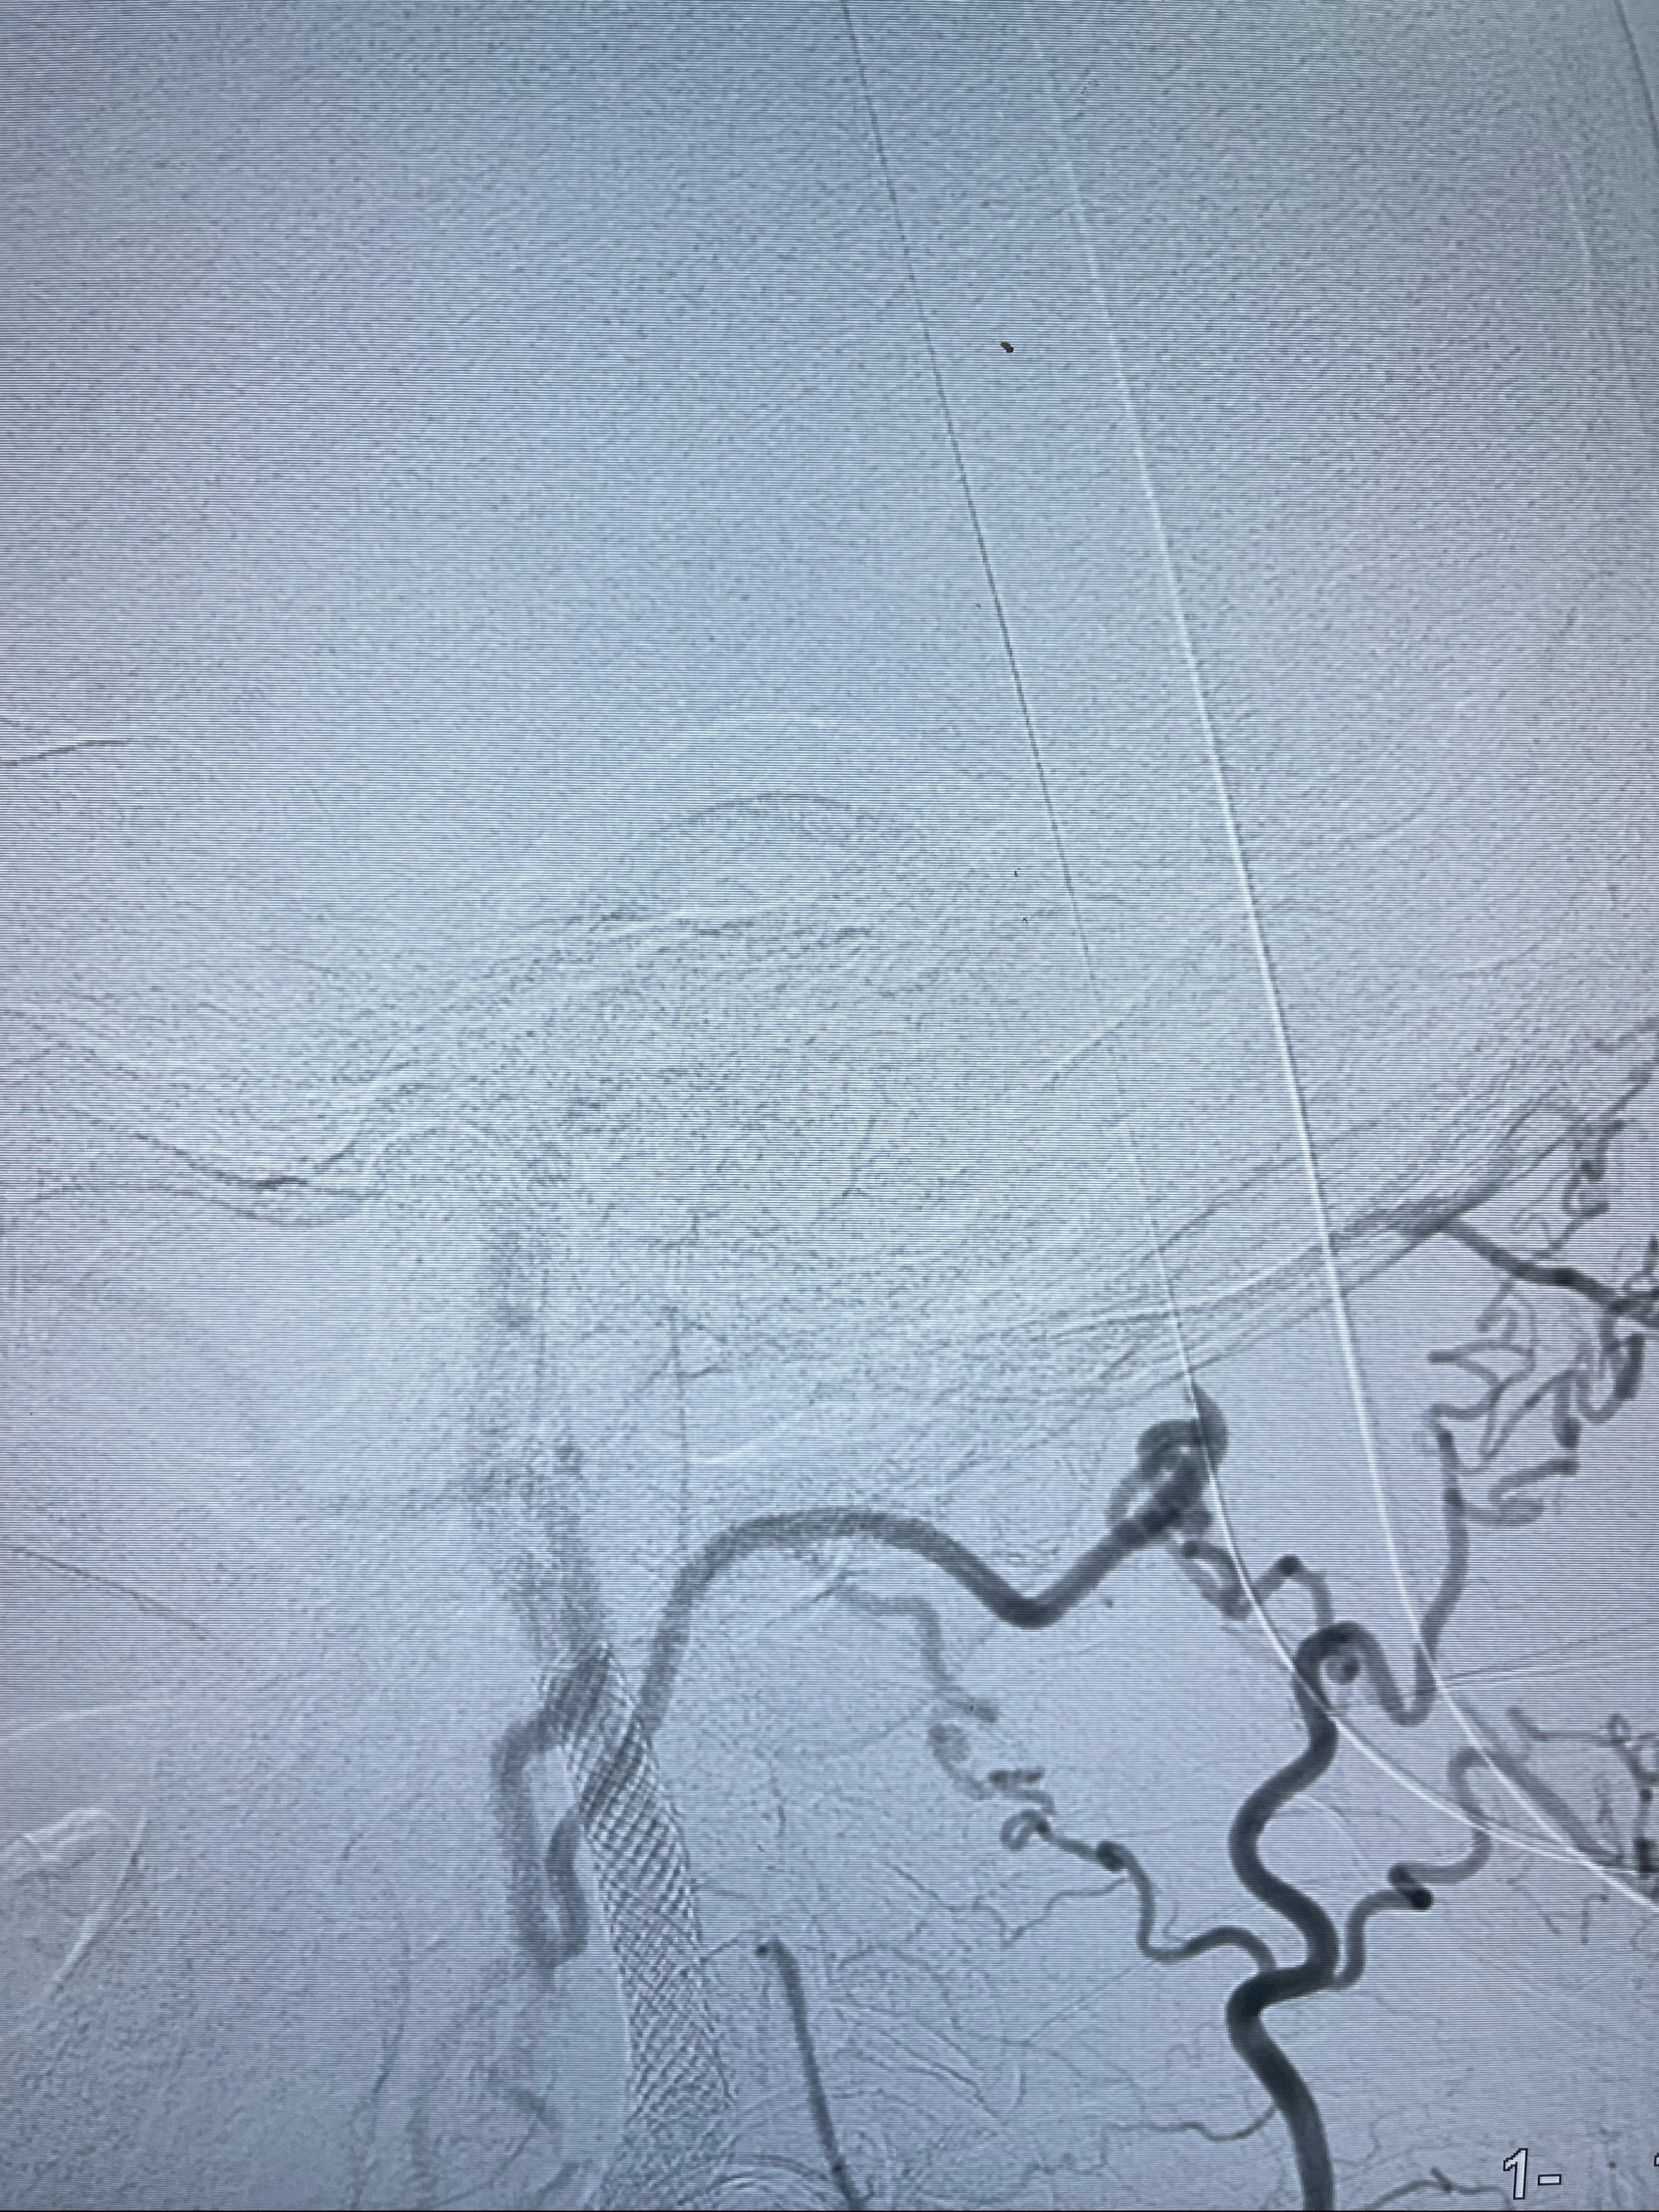

重新行“路径图”,支架导管在微导丝引导下超选择性插入至右侧颈内动脉眼段,4.5-50mmLeo支架释放,远心端位于海绵窦段,近心端位于岩骨段狭窄段以近

即刻造影显示支架贴壁佳

路径图下,5.5-50mmLeo支架导管在微导丝引导下超选择性插入远段Leo支架内

两枚支架部分重叠

多次确认支架位置及打开贴壁情况

支架完全打开,近心端位于原颈动脉支架远心端内